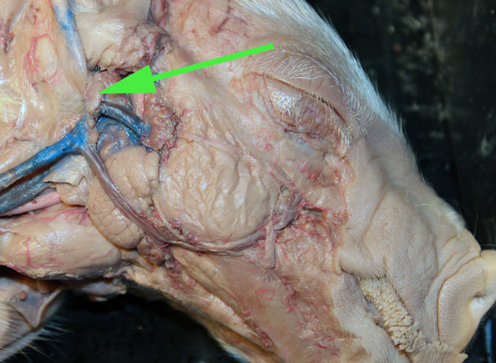

The vessel marked by the green arrow is a coronary artery

The artery marked by the green arrow is the common carotid artery.